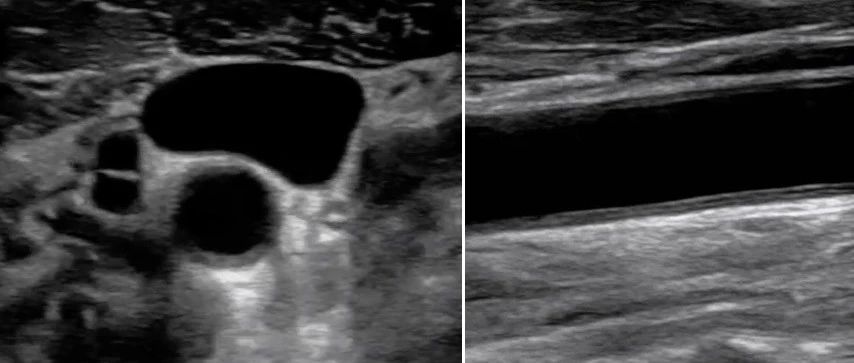

【力学笃行】重症超声的血管评估

床旁重症超声已经迅速成为重症医学科医护的一项重要工具,血管评价是其非常重要的一部分,是血管通路选择及穿刺置管、静脉血栓形成诊断和治疗及血流动力学评价等的基础。美国胸科医师协会、世界重症超声联盟等组织均将血管评价作为重症医生必须掌握的一部分。静脉血栓栓塞症(VTE)作为重症患者住院期间常见并发症,在未明确诊断的情况下可以增加患者病死率。急性肺栓塞患者中90%栓子来源于下肢近端深静脉血栓。DVT作为一种隐匿性极强的并发症,早预防,早发现,早治疗是降低患者死亡风险的重要措施。...